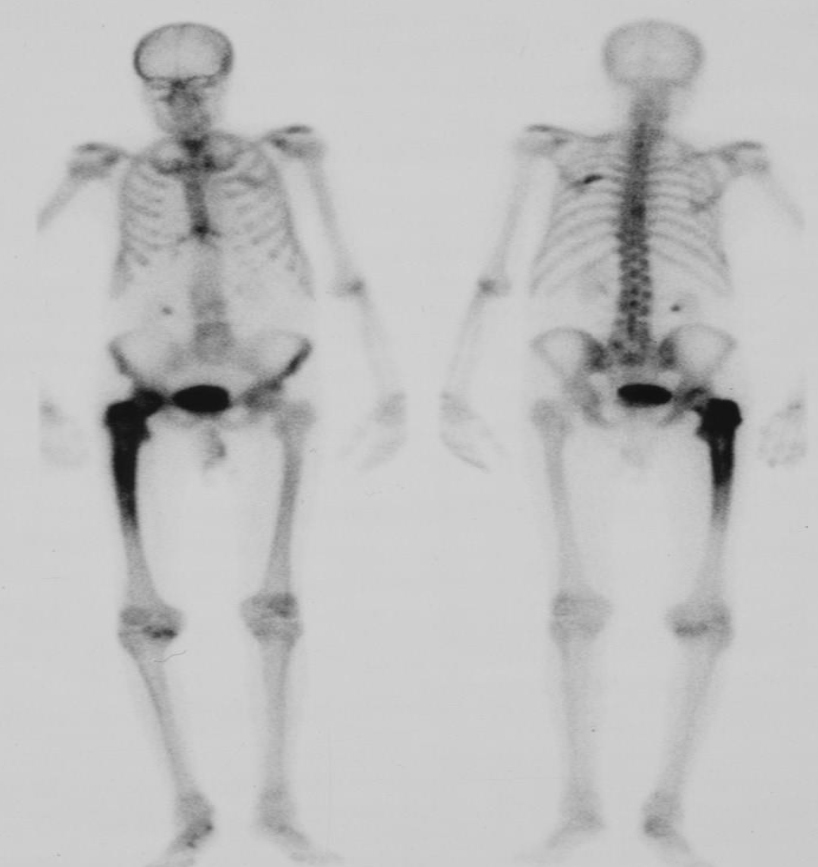

A. Give the name of the used imaging modality

SCINTIGRAPHY /RADIONUCLIDE BONE SCAN

B. What is the most probable diagnosis ? Metastasis

C. Describe the abnormality. Multiple areas of increased uptake